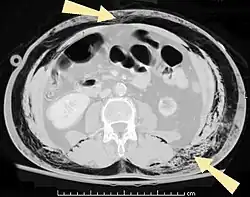

| An abdominal CT scan of a patient with subcutaneous emphysema (arrows) | |